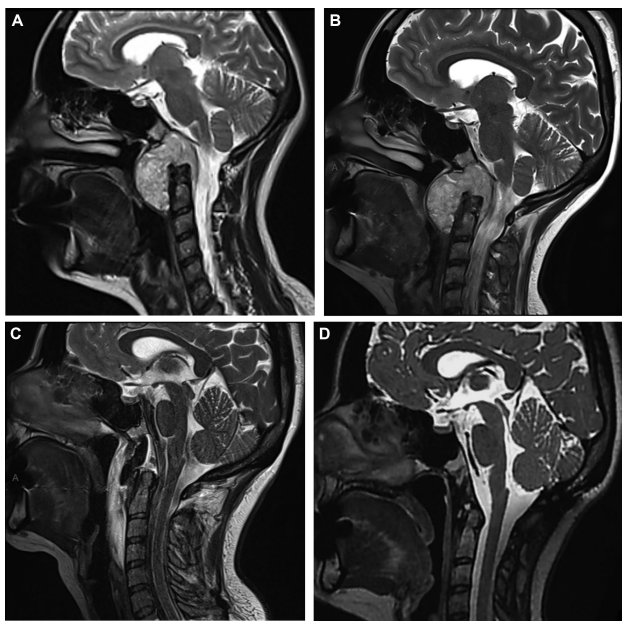

图示:MRI 显示一例颅颈交界区(CVJ)脊索瘤,其术前肿瘤生长速率(TGR)较低(3.53%/月)。

A:手术前 3 个月;

B:术前 1 天;

C:术后 48 小时,提示肿瘤全切除(GTR);

D:术后 14 个月(术后已行质子放疗 PBT),未见肿瘤复发。